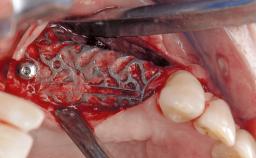

Treatment of Peri-Implant Mucositis at a Zirconia Implant

Recent clinical studies, most with short-to-medium term observation periods, have reported on the favorable clinical performance of zirconia implants in terms of survival rates, clinical, and radiographic outcomes (Roehling and coworkers 2016; Roehling and coworkers 2017; Rodriguez and coworkers 2018; Lorenz and coworkers 2019). Nonetheless, a rather high incidence of peri-implant disease at zirconia implants (39% of implants) was noted throughout a two-year period, highlighting the need for treatment protocols of peri-implant diseases at zirconia implants (Becker and coworkers 2017).